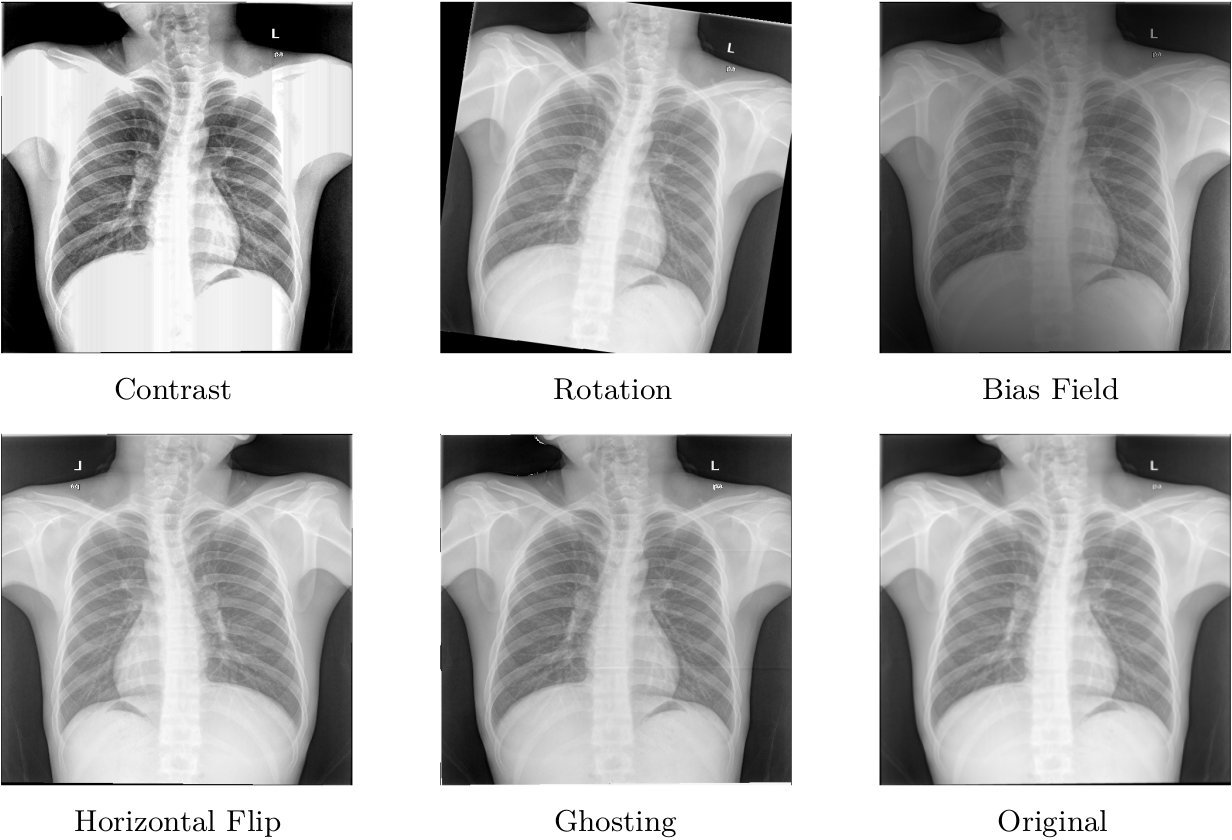

Then, an evaluation was performed on the prepared test data. It contained both original and augmented images. For every pair of ground-true and predicted mask, the quality of segmentation was assessed using dice similarity coefficient [10] and intersection over union (IoU). The following augmentations, presented in Figure 1, were done: contrast, random rotation, bias field, horizontal flip, and discrete "ghost" artifacts. The resulting dataset allowed us to perform testing on model behavior when presented with an image with augmentation that was not present in the training phase.

Refer to caption

Figure 1: Types of augmentation on which the ability to adapt to new conditions of segmentation models was tested.